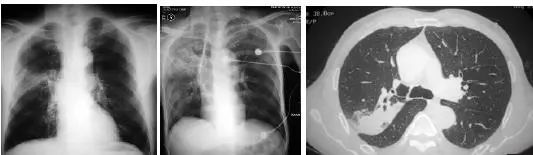

患者急性起病,发热,咳嗽,咳痰,痰液粘稠。

诊断啥?

肺炎克雷伯杆菌,是肺炎常见细菌,典型的影像学表现是叶间裂下坠。什么是叶间裂下坠?书上只有文字,我也可以意会到,然而画面很模糊。多年以后,我才突然秒懂!

一般情况下,克雷伯杆菌肺炎的影像学表现与其他细菌性肺炎相似, 仅根据影像鉴别相当的诊断困难,但是,知道其特点,才能发现典型的患者,有时候可以更好的早期诊断,减少抗生素滥用,为人民服务!

比如上面的患者,假如了解肺炎克雷伯杆菌的特点,至少,初始治疗就不用广泛的使用抗生素,从而实现现在很流行的精准治疗。